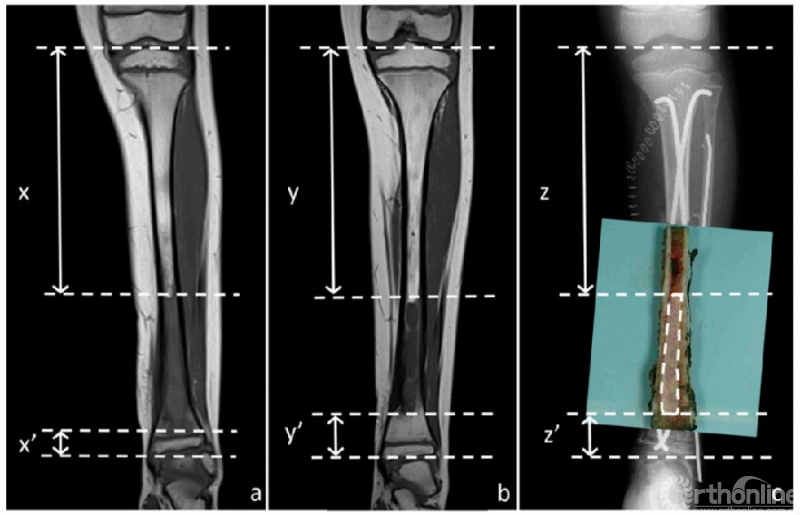

由放射科医生以标准化方式对化疗前、后的MRI进行分析。研究纳入了三个MRI序列:T1加权、T1增强以及STIR序列。对于每个序列,通过冠状面上的异常信号和正常信号来确定肿瘤的范围。测量骨内异常信号的近端和远端边界与相应的骨末端之间的距离(图1A和1B)。

图1 8岁男孩左胫骨尤文氏肉瘤。图1A,化疗前T1加权。表示骨近端到肿瘤近端界限的距离(x)和骨远端到肿瘤远端界限的距离(x’);图1B,化疗后T1加权。表示骨近端到肿瘤近端界限的距离(y)和骨远端到肿瘤远端界限的距离(y’);图1C,显示组织学测量。在本例中,近端(z)和远端(z’)测量值表示各自肿瘤极限与手术标本上切割的骨之间的距离,加上计算机X光片上测量的残骨长度。

在切除的标本上,测量了肿瘤边界(近端和远端)与相应骨末端之间的距离。当末端包括骨骺时,这种组织学测量就足够了。当末端是骨切面时,在组织学测量中添加了术后X线检查中测量的骨切面与残余骨末端之间的距离。这2个距离的总和对应于肿瘤相对于骨末端的距离(图1C)。

为了评估MRI确定肿瘤边界的准确性,研究探讨了每次MRI测量与组织学测量之间的差异。当MRI边界相对于组织学边界处于正常区域时值为负值,当MRI边界在肿瘤区域内时评分为正值。